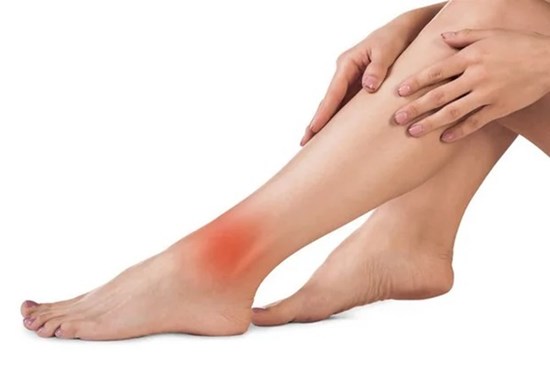

3 đặc điểm ở bàn chân cảnh báo mạch máu bị tắc nghẽn, phát hiện sớm sẽ cứu được bạn

Mạch máu là đường ống lưu thông máu trong cơ thể chúng ta. Trên thực tế, vai trò của mạch máu là phân phối các chất dinh dưỡng đến các bộ phận khác nhau trong cơ thể.

3 dấu hiệu bất thường ở tay chân: 80% khả năng bạn bị tắc mạch máu, nên xử lý ngay

Sức khỏe của mạch máu thường đi cùng với tuổi thọ của bạn. Khi mạch máu có vấn đề, sức khỏe sẽ ảnh hưởng nghiêm trọng. Nếu có 3 dấu hiệu này, bạn nên đi khám ngay.